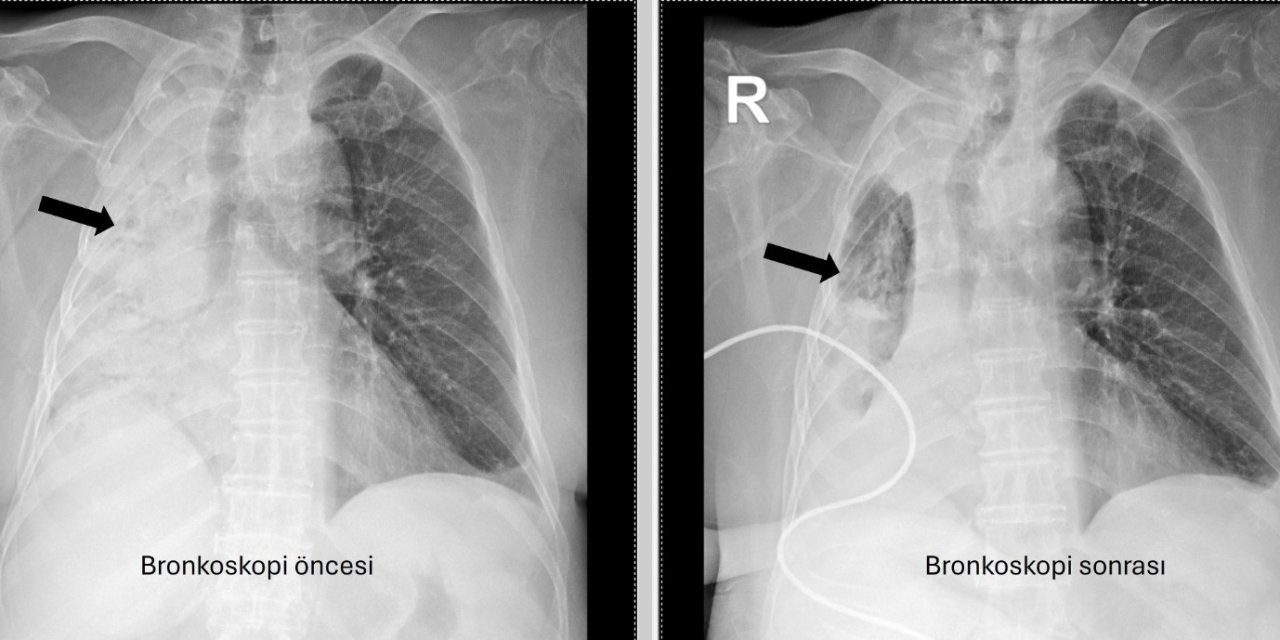

5 ay önce yediği pizza akciğerini tamamen kapattı